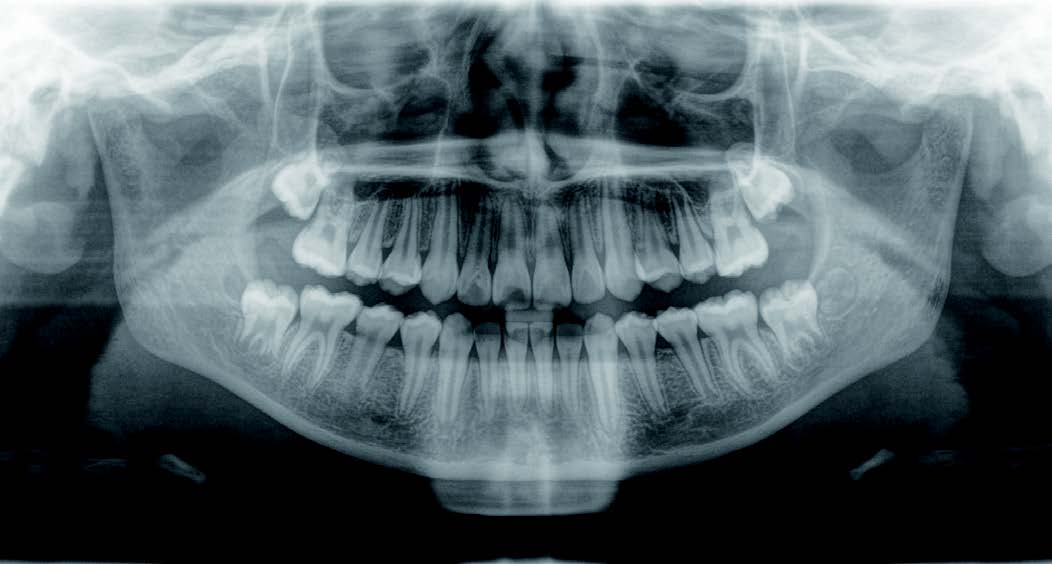

下の奥歯が内側に傾いて、舌の位置が悪く、鼻がつまって口呼吸の状態でした。扁桃腺がよく腫れ、風邪をひきやすく、いびきもあるようでした。